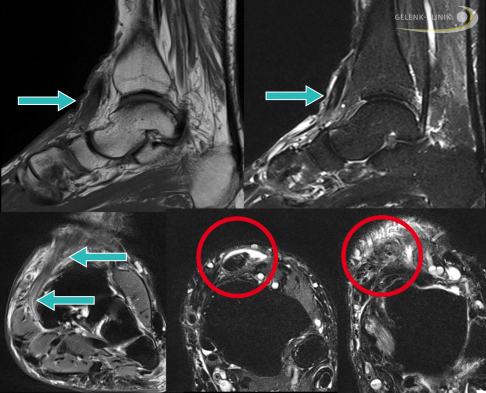

Um Lokalisation und Ausmaß der Sehnenschädigung richtig einschätzen zu können, sind bildgebende Verfahren wie Ultraschall und MRT (Magnetresonanztomografie) indiziert. Anhand der Bildgebungen kann der Arzt die Durchgängigkeit der Tibialis-anterior-Sehne und ihre Struktur beurteilen. Auch mögliche Veränderungen der umliegenden Weichteile (z. B. Sehnenscheiden) können auf diese Weise sichtbar gemacht werden.

Reißt die Tibialis-anterior-Sehne ein, bleibt das verdickte Ende des Sehnenstumpfes häufig an einem der Haltebänder (Retinakula) der Sehne hängen. An dieser Stelle entsteht eine Schwellung, die der Fußspezialist durch die Haut ertasten kann. Anhand seiner Einschätzung kann er dann die Rekonstruktion der Sehne vornehmen.